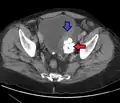

- Los divertículos vesicales son crecimientos en forma de globo en la vejiga comúnmente asociados con obstrucción crónica del flujo de salida, como hiperplasia benigna de próstata en hombres mayores. Por lo general, se encuentran en pares en lados opuestos de la vejiga. Los divertículos de la vejiga a menudo se extirpan quirúrgicamente para prevenir infecciones, rupturas o incluso cáncer.

Divertículo de la vejiga urinaria de un hombre de 59 años, plano transversal